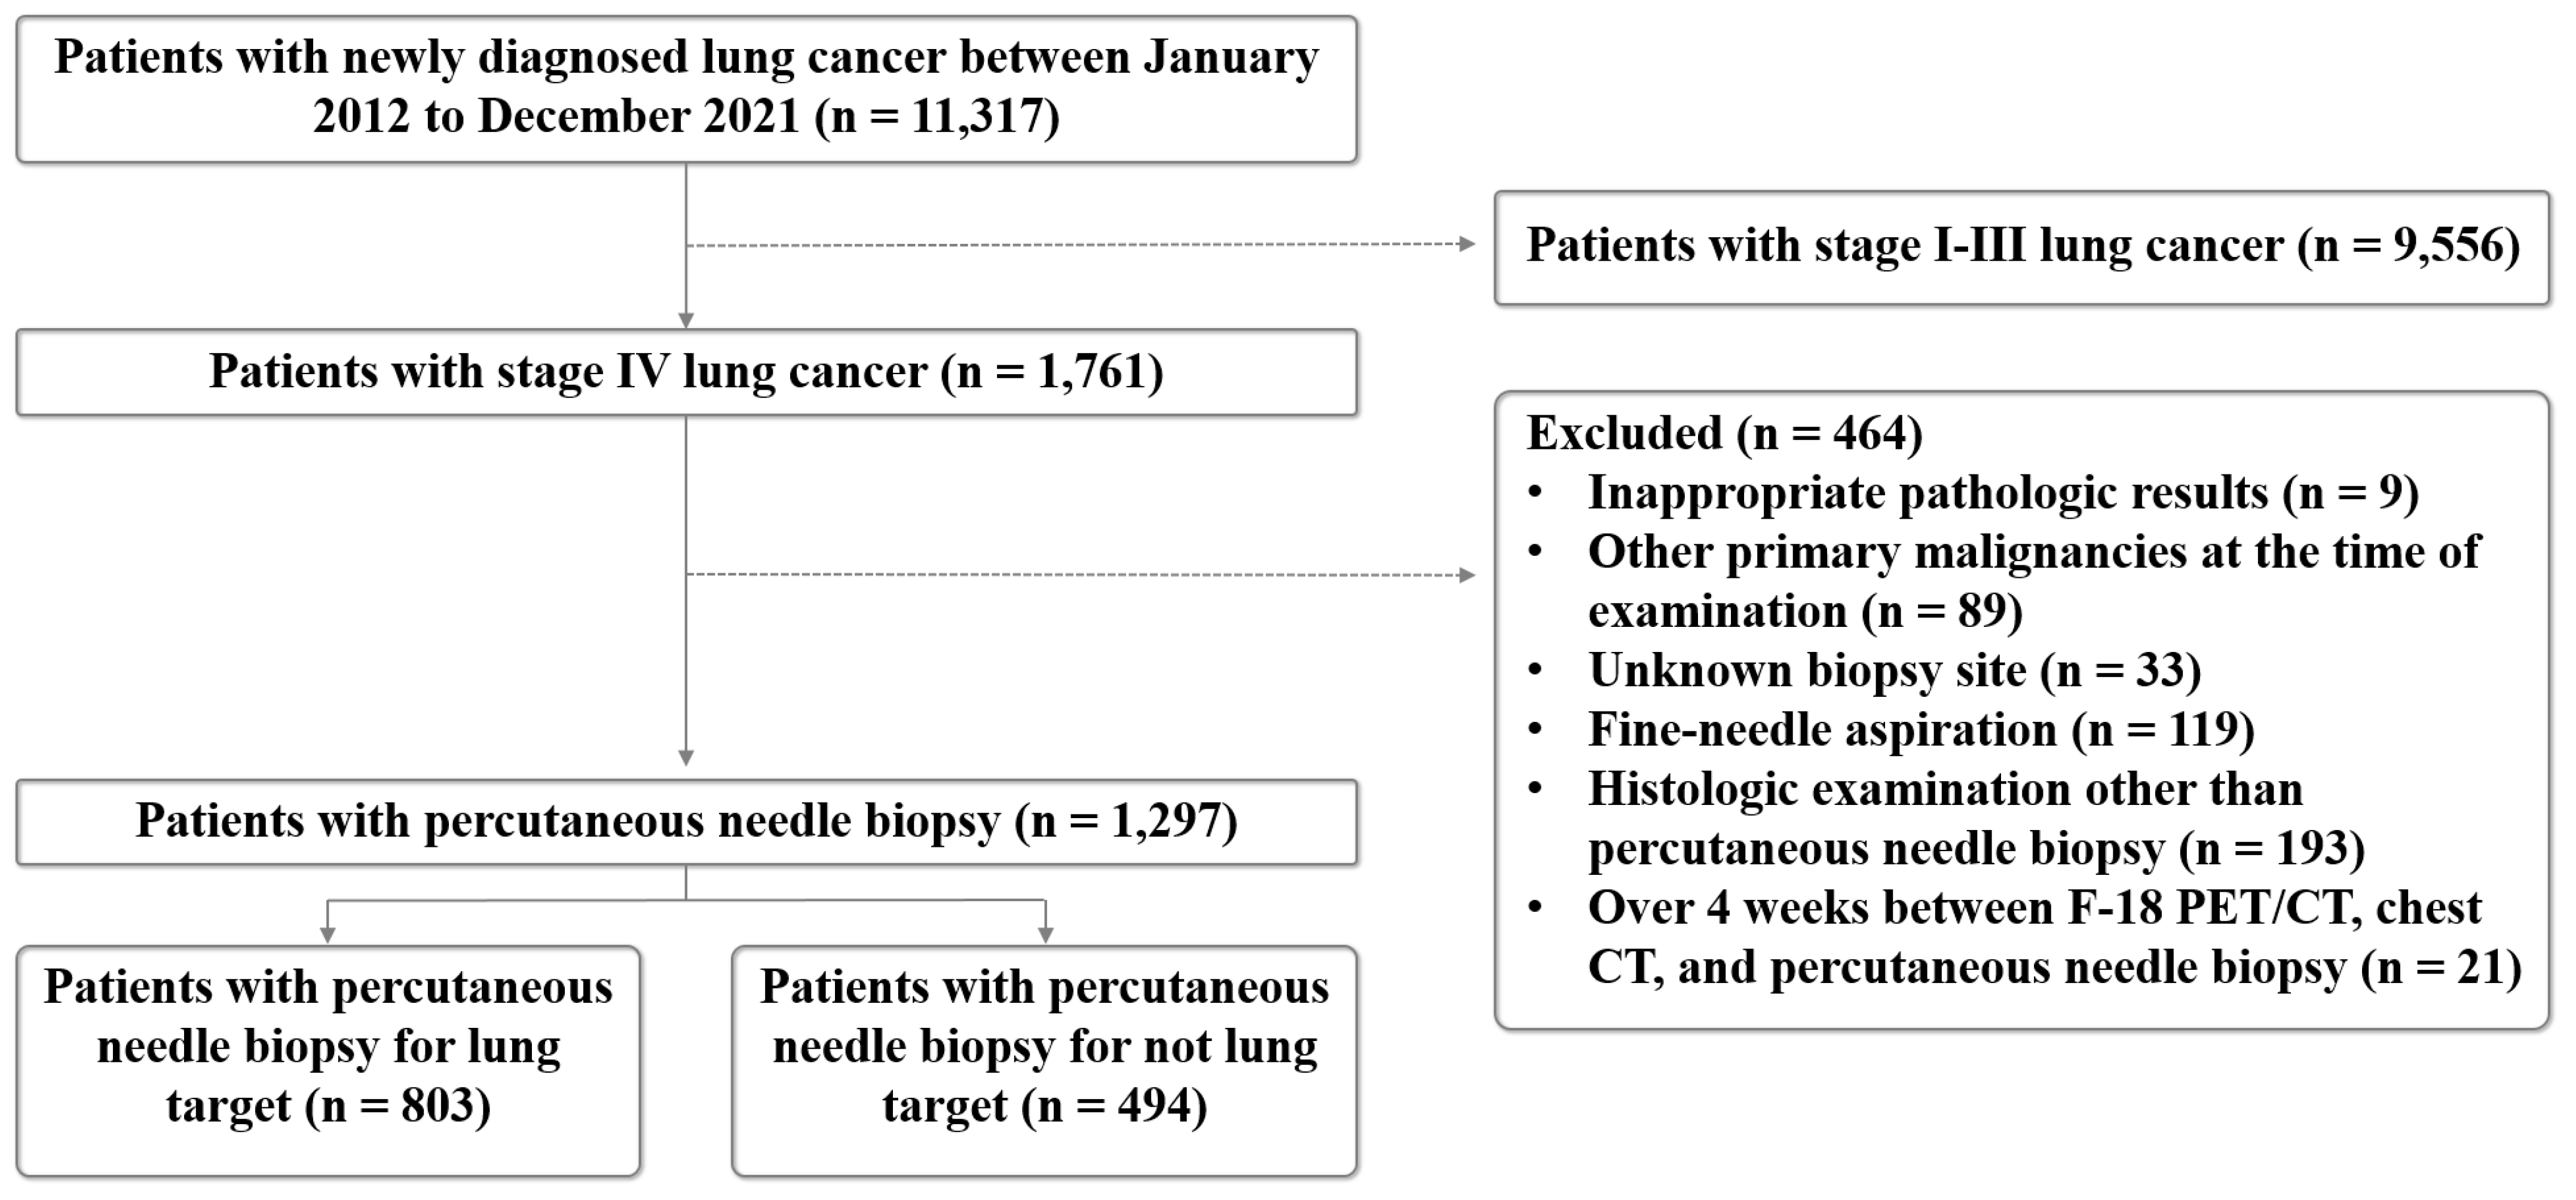

2.1. Study Population